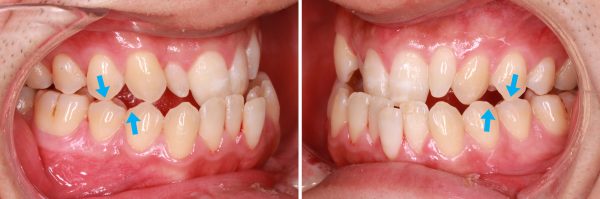

11歳 女性 「噛み合わせが反対で食事しにくい」( 前歯の欠損症例 )

11歳 女性です 「噛み合わせが反対で食事しにくい」との事で来院されました。

前歯部と側方歯の 反対咬合(受け口)です。

じっくりと確認してみますと、左上側切歯がありません。

欠損でしょうか? 埋伏歯でしょうか?

こういった場合は歯科用CTで確認します。

左上側切歯(前から2番目の歯)は先天的な欠損歯であることが判明しました。

先天欠損とクロスバイトを伴う反対咬合症例

わきの歯がほとんど噛み合っていませんので食事はしにくいです。

1本歯が欠損していると歯並びが成立しなくなります。

欠損している歯のスペースを開けてキチンと排列しました。

治療期間12か月

2016年の2月26日にスタートして

2017年の2月17日に終了しました。

反対咬合とクロスバイトは解消されました。 (#^.^#)

わきの歯はキッチリと噛み合いお食事がとても美味しくなったそうです。

欠損歯は将来的(成人してから)にインプラントなどの補綴処置を行う予定です。

現在は顎の成長に対応できるように暫間的な歯を装着しています。

スマイルラインが幅広くなり、素敵な笑顔になりました。 (#^.^#)

11歳 女性 欠損歯を伴う反対咬合 治療期間12か月 唇側矯正装置(ホワイトワイヤー)を使用した非抜歯治療 参考治療費 約61万円 (精密検査から終了まで) 矯正治療に伴う副作用の歯肉退縮、知覚過敏、歯根吸収などは認められませんでした。